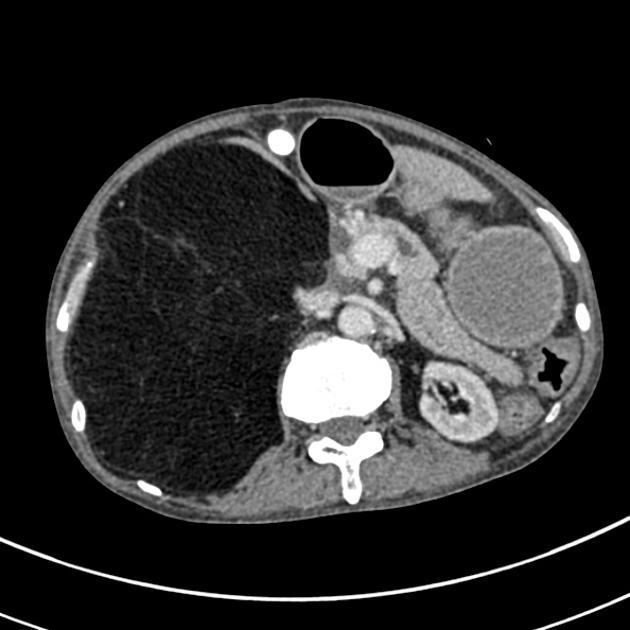

Patient with shock and abdominal pain. Diagnosis?

Ruptured AAA.